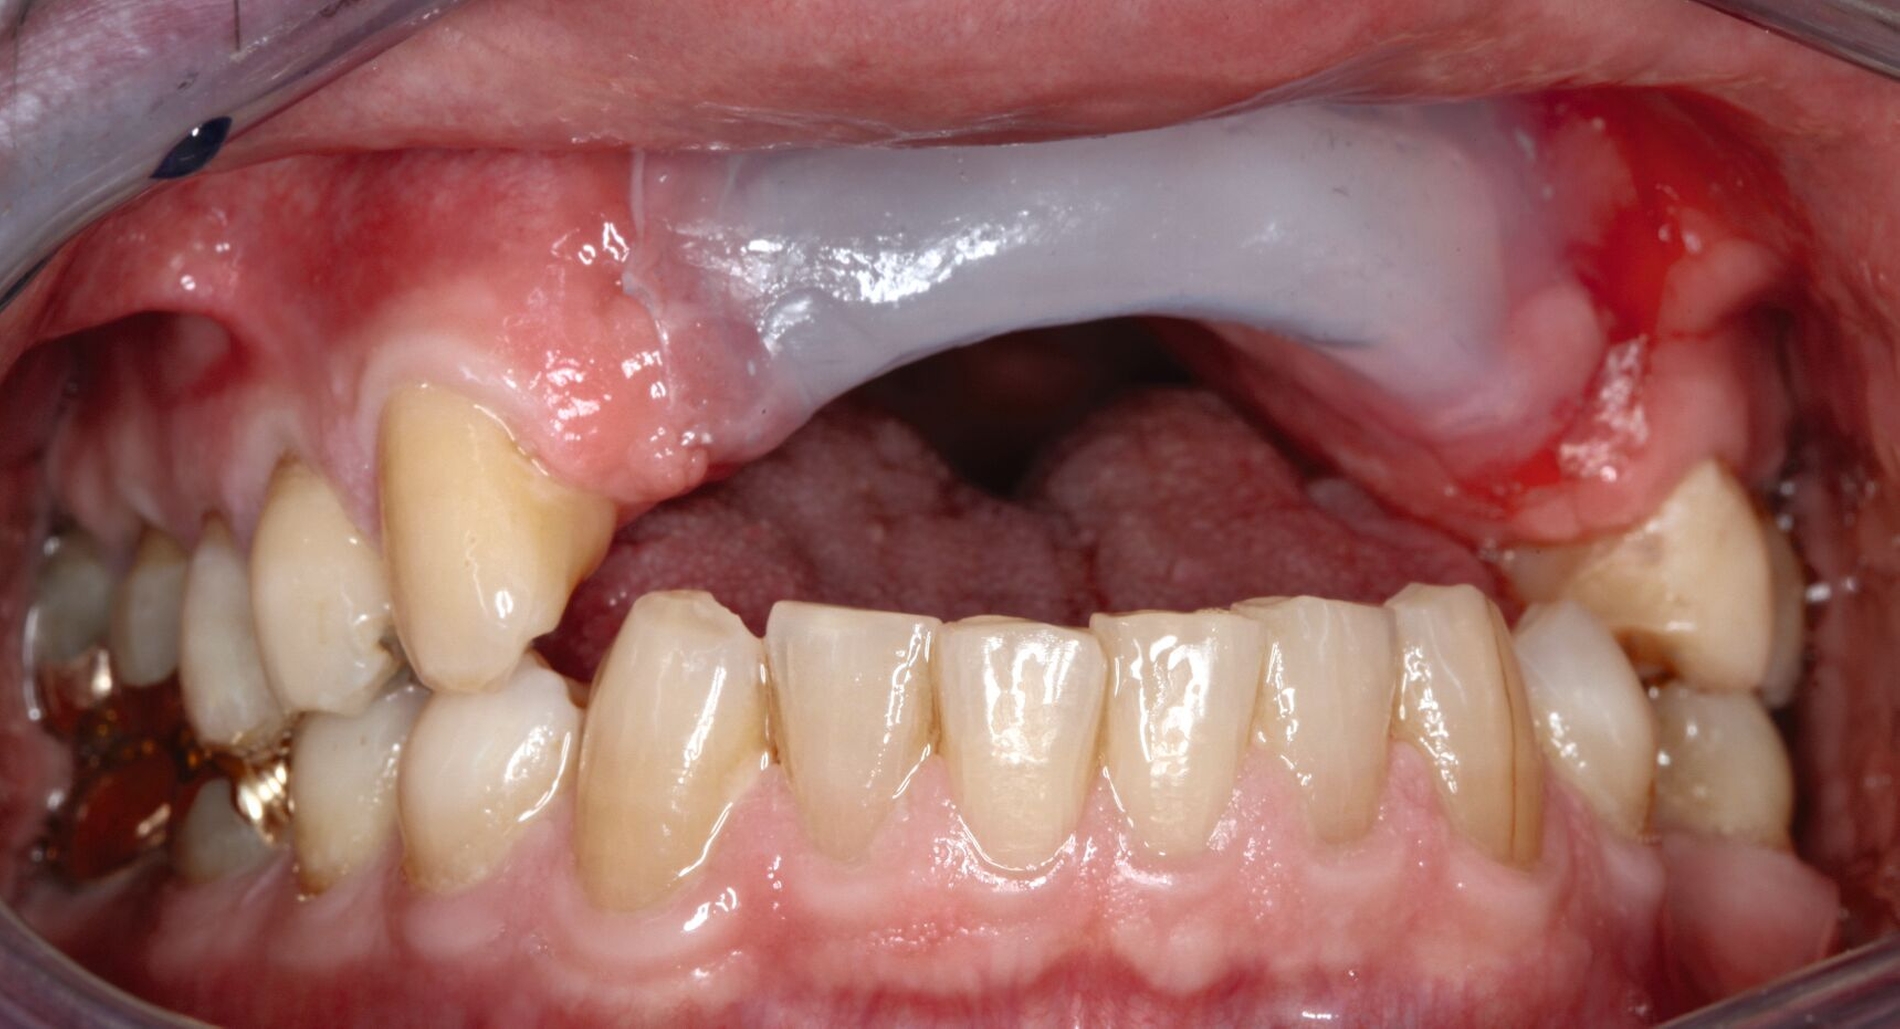

Mit Einbringen eines Wendel-Tubus zur Sicherung der Atemwege, lässt sich der Defekt ohne Probleme abformen (Abbildung 3). Jener verhindert auch, dass der spätere Silikon-Obturator die Atemwege nicht verlegt. Speziell visköses Silikon-Abformmaterial („Laborsilikon Orange“, 12 Shore A, Institut für Anaplastologie Schilling, Würzburg, Deutschland) verhindert ebenfalls, dass die Abformmasse in Richtung des Pharynx fließt. Nach der Defektabformung können die herkömmlichen Arbeitsschritte für einen Zahnersatz (als Zusatz zum Silikon-Obturator oder zur Herstellung einer Obturator-Prothese) erfolgen.

Sowohl ein Silikon-Obturator als auch eine Obturator-Prothese müssen nach der Tumoroperation häufig angepasst werden, um einen nasalen Reflux zu vermeiden, da sich der Defekt mit eintretender Wundheilung gerade in den ersten Monaten sehr stark verändern kann [Moreno et al., 2010]. Beide Alternativen geben die Möglichkeit, Weichgewebedefekte aufzufüllen und die fazialen Anteile wiederherzustellen [Ali et al., 1995]. Nachteilig ist dagegen eine oft (schmerzhafte) Krustenbildung im Bereich des Defekts.